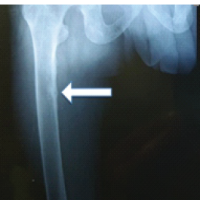

Initially, the bulk of the reamer head was removed by retracting the ball-tip guide wire; however, four small metal pieces remained in the canal (Fig. 2a). Next, a removal attempt using a series of differently sized graspers was made; however, this was only partially successful and very time-consuming (Fig. 2b). Then, the idea of extracting the debris using a laparoscopic suction instrument (Stryker® Inc) (Fig. 3) under fluoroscopy was conceived and successfully put into practice (Fig. 2c). Finally, once the canal was clear (Fig. 2d), a new RIA-2 set was used, and the procedure was completed successfully. The patient was given broad-spectrum antibiotics until speciation of cultures and was allowed to weight bear as tolerated on the right lower extremity.